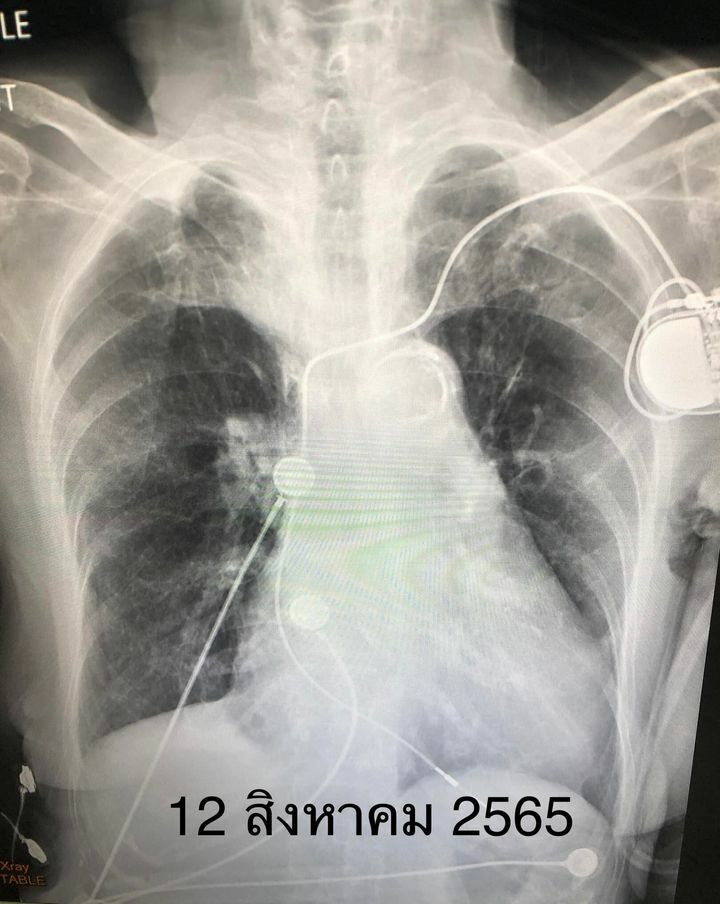

A 90-year-old Thai female patient suffering from hypertension. hyperlipidemia irregular heartbeat insert a pacemaker Never received a single dose of the coronavirus vaccine. Infected with covid from a 13-year-old grandson on July 31, 2022, came to the hospital with nausea and vomiting. Later, there was high fever, breathlessness, very low oxygen level. The first ATK test was negative, but the RT-PCR SARS-CoV2 CT value N gene 10.23 on the lung X-ray had white melasma on the right side more than the left side (see picture), requiring coughing. CU Administered high-flow nasal cannula, received remdesivir injection for 5 days, fever decreased, fatigue improved. X-rays of the lungs are greatly reduced (see figure), oxygen levels return to normal without oxygen. After being in the hospital for 13 days